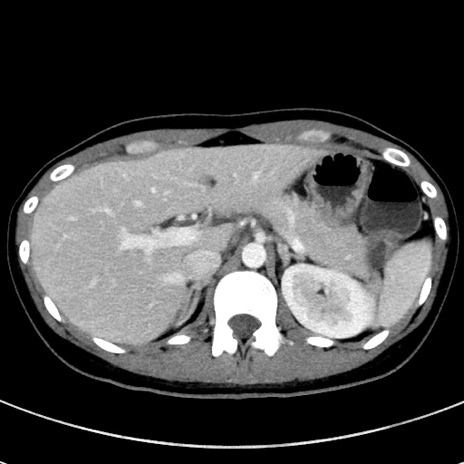

症例17(横断像)

【症例】20歳代女性

【主訴】嘔吐、下腹部痛

【現病歴】昨日夕食後に嘔吐し下腹部痛が出現。本日になっても嘔吐持続し改善しないため来院。

【身体所見】意識清明、BT 37.2℃、BP 108/67mmHg、腹部:平坦、やや硬、下腹部正中から右にかけて圧痛あり、反跳痛軽度あり、tapping pain(+)。

【データ】WBC 13600、CRP 14.94